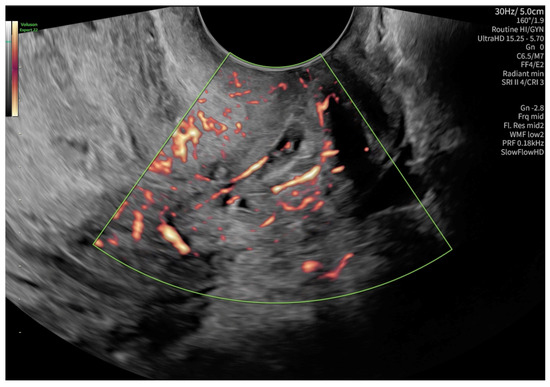

2. Case Presentation